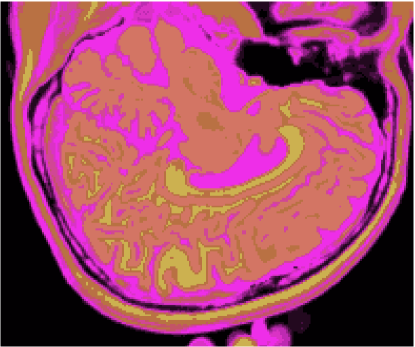

As figuras 2 (banda 0), 3 (banda 1) e 4 (banda 2) mostram a fatia 97 de um volume de imagens sagitais com 181 fatias e 0% de ruído, ponderadas em PD (densidade de próton), T1subscript𝑇1T_{1} e T2subscript𝑇2T_{2}, enquanto a figura 5 ilustra a composição colorida R0-G1-B2 da mesma fatia. Pode-se notar no topo do crânio, na parte inferior das imagens, a presença de artefatos, que podem ser resultantes de erros no simulador, mas que não são prejudiciais à análise, uma vez que, neste trabalho, não é dada ênfase à análise anatômica.

Refer to caption

Figura 5: Composição colorida R0-G1-B2 das imagens da fatia 97 ponderadas em PD, T1subscript𝑇1T_{1} e T2subscript𝑇2T_{2}